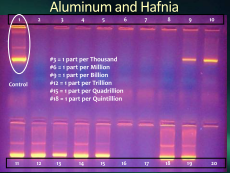

Composites without aluminum

providing toxicity to overcome

At doses that are really small

parts per quintillion that still appall

Doses that small seen on our gels

can kill our active immune white cells